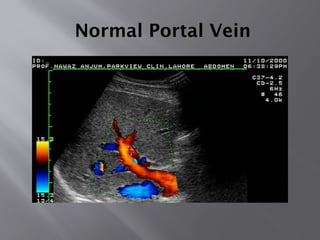

Normal Portal Vein